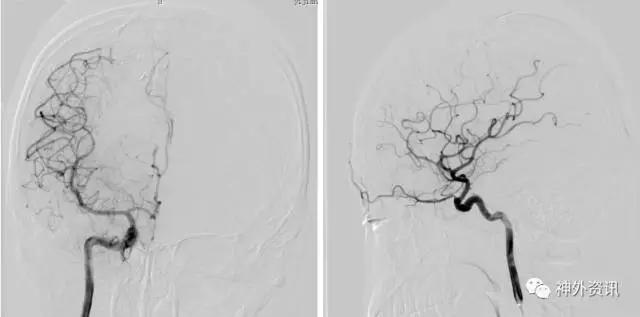

1例左侧额颞顶部巨大AVM

(3D血管融合:左侧额颞顶部巨大AVM,大小约10.4*6.7*5.7cm)

(治疗中,ENVOY DA导引导管置于左侧大脑前动脉A1段)

(SONIC 导管顺利超选至畸形血管巢,并且拔管顺利)

1例右侧额叶AVM伴右侧额叶血肿

(挑战:终末血管供血,超选距离遥远,途经血管迂曲,选择使用Envoy DA)

(Envoy DA导引导管—右侧大脑前动脉A1段)

(成功超选,栓塞后拔管顺利)

栓塞术后畸形团少量残留,静脉引流通畅,后2期行手术切除,术后复查脑血管造影畸形团未见明显残留。